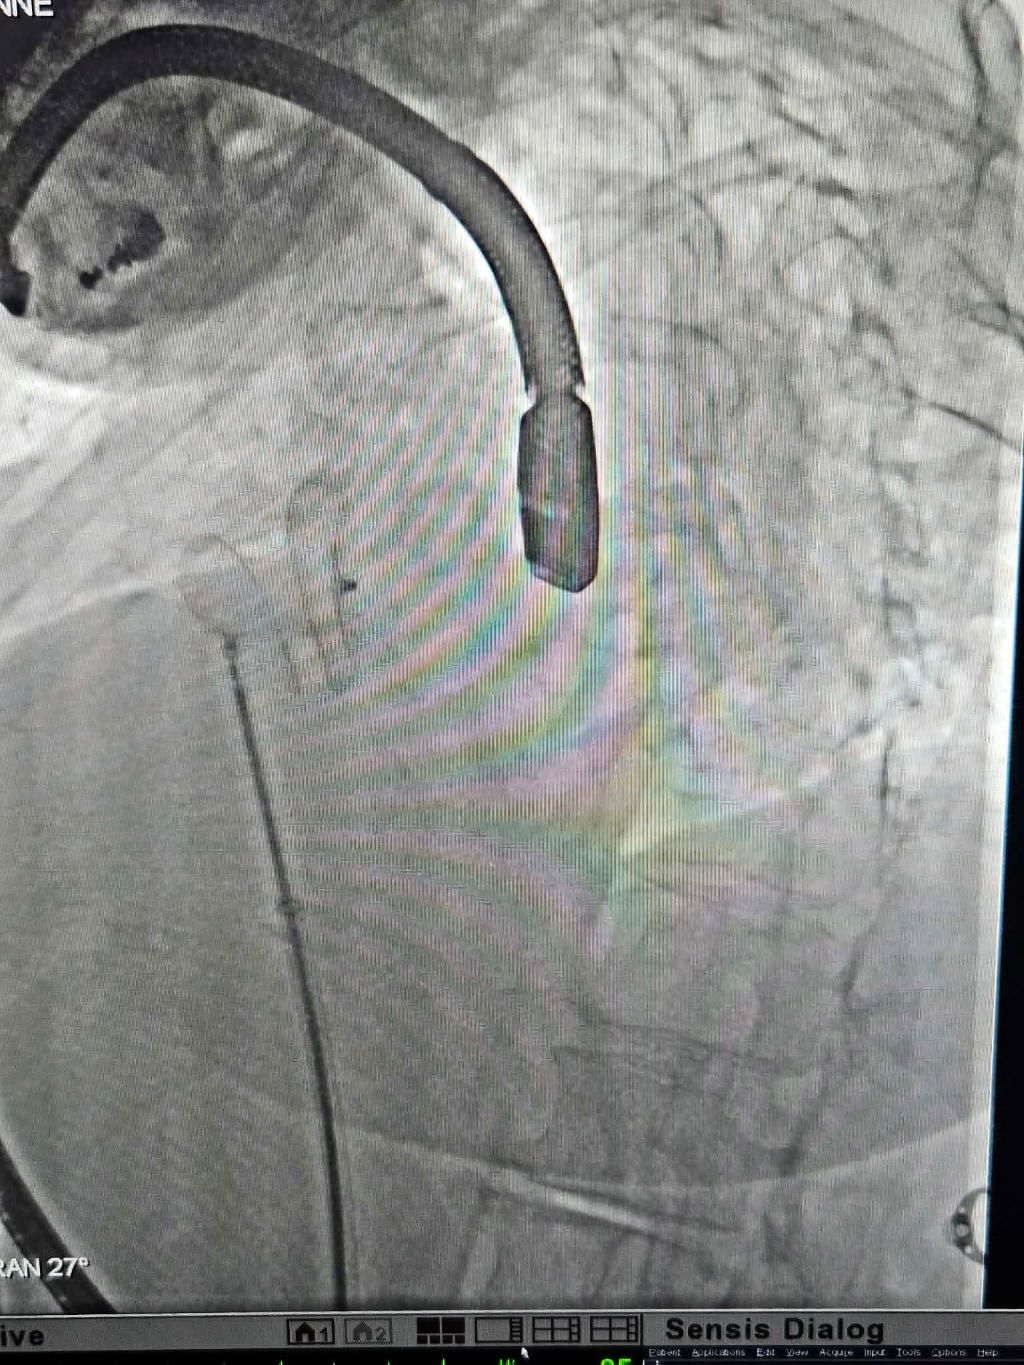

Πρόκειται για διαδερμική σύγκλειση μεσοκολπικής επικοινωνίας, μιας από τις πιο κοινές συγγενείς καρδιοπάθειες, μια εξειδικευμένη και υψηλής τεχνικής δυσκολίας επέμβαση, η οποία πραγματοποιήθηκε για πρώτη φορά με επιτυχία στην περιοχή, αποκλειστικά στο ΙΑΣΩ Θεσσαλίας, στο υπερσύγχρονο Αιμοδυναμικό Εργαστήριό του.

Υπεύθυνος ιατρός της επέμβασης ήταν ο κ. Νίκος Μαγκούτης, MD, MSc, PhD, Επεμβατικός Καρδιολόγος, Διευθυντής και Επιστημονικά Υπεύθυνος του Αιμοδυναμικού Εργαστηρίου, με τη συνεργασία εξειδικευμένης ομάδας ιατρών. Ειδικότερα, στην επέμβαση συνέβαλλαν ο κ. Όμηρος Χαλβατζούλης Χειρουργός Θώρακος Καρδιάς Μεγάλων Αγγείων, Επιστημονικά Υπεύθυνος Καρδιοθωρακοχειρουργικού Τμήματος, η Αναισθησιολόγος Σμαραγδή Σαρχώση, ο Καρδιολόγος Αργύρης Γκαρμπούνης, η Αναισθησιολόγος Ευαγγελία Νέου και η ομάδα των εξειδικευμένων τεχνολόγων και νοσηλευτών του Αιμοδυναμικού Εργαστηρίου του ΙΑΣΩ Θεσσαλίας. Στην επέμβαση συμμετείχε και ο κ. Βασίλειος Θανόπουλος, Αναπληρωτής Καθηγητής και Επεμβατικός Καρδιολόγος Συγγενών Καρδιοπαθειών, με πολυετή εμπειρία σε σύνθετες διακαθετηριακές επεμβάσεις.